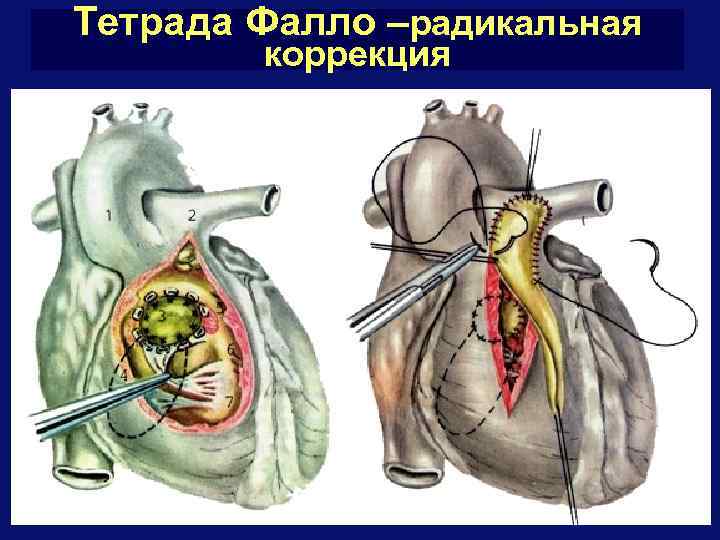

Тетрада Фалло –радикальная коррекция